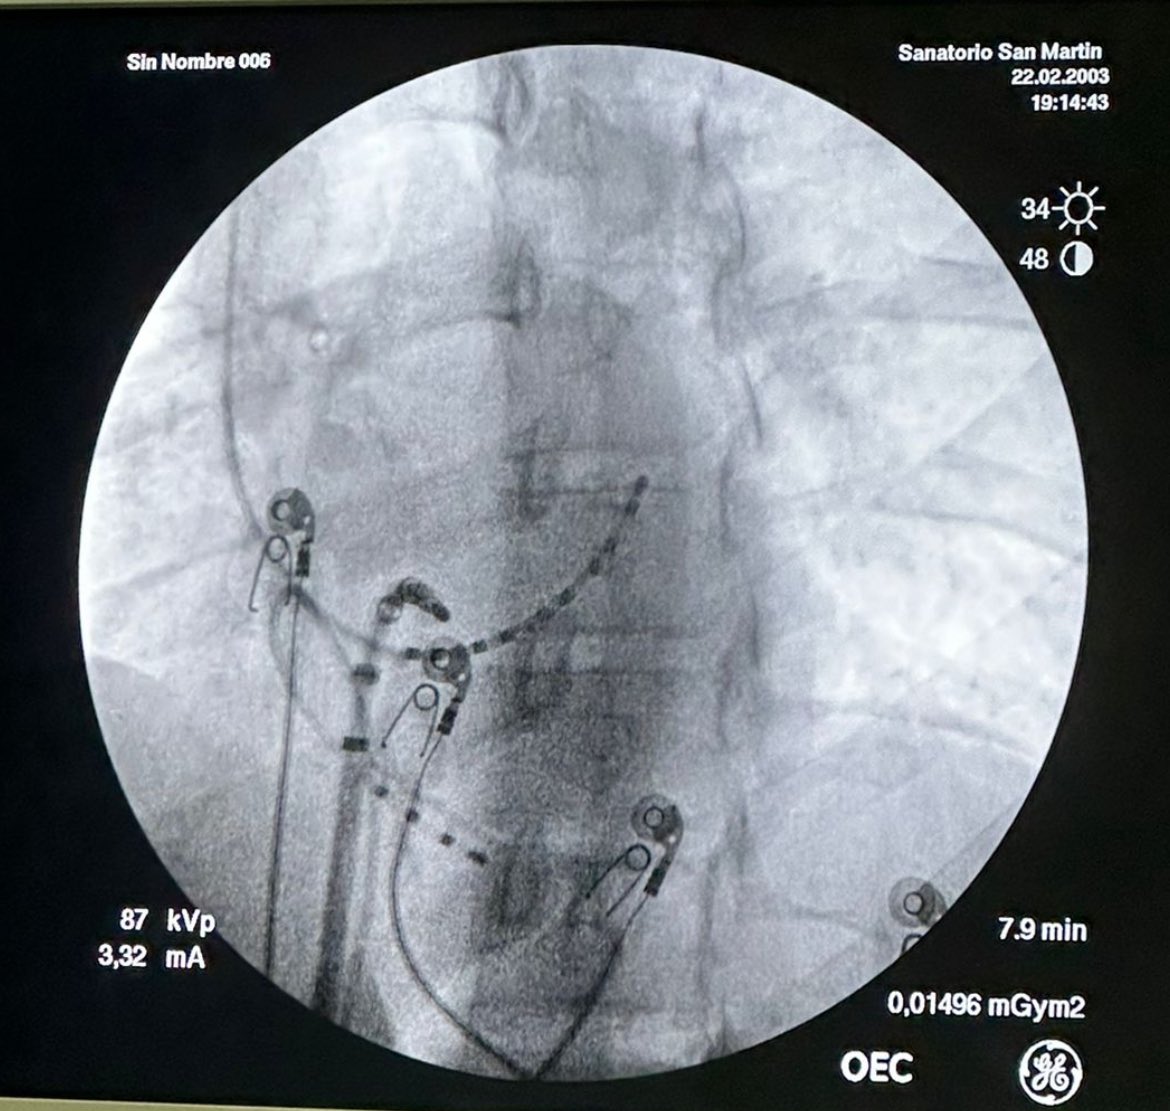

#WPW Slanted Left posteroseptal AP. Case from last week. Assessment of oblique course of AP during Sinus Rhythm and V pacing. There is a mismatch in earliest A EGM during V pacing and V far field EGM during Sinus Rhythm. This will make you know where to aim the RFA.

#WPW

Slanted Left posteroseptal AP. Case from last week.

Assessment of oblique course of AP

during Sinus Rhythm and V pacing.

There is a mismatch in earliest A EGM during V pacing and V far field EGM during Sinus Rhythm.

This will make you know where to aim the RFA.

RFA performed close to V insertion mapping the earliest V during sinus rhythm at posteroseptal level as depicted in sinus rhythm EGM. Ablation catheter is not at earliest A during V pacing. All starts with EGM analysis. Success at first session.

RFA performed close to V insertion mapping the  earliest V during sinus  rhythm at posteroseptal level as depicted in sinus rhythm EGM.

Ablation catheter is not at earliest A during V pacing.

All starts with EGM analysis.

Success at first session.